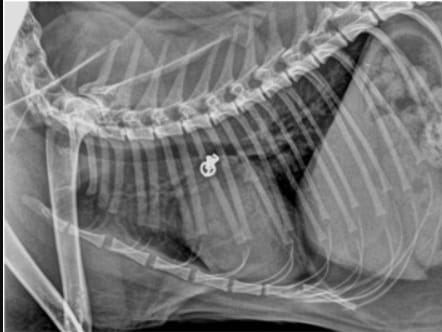

Lateral thoracic radiograph following the procedure and confirming adequate placement and location of the Vet-PDA Occluder™ device.

A five-month-old female domestic short-haired cat, weighing 2.22 kg, was referred for evaluation of a continuous heart murmur. Transthoracic echocardiography confirmed a left-to-right shunting PDA. The procedure involved a transjugular approach using fluoroscopic guidance. A 6×5-mm Vet-PDA Occluder™ was deployed via a 4-Fr catheter into the descending aorta, with subsequent repositioning into the pulmonary ostium. The procedure was monitored using angiography and Doppler echocardiography.

The device was successfully deployed, leading to the immediate resolution of the heart murmur. Postoperative echocardiography revealed mild residual blood flow through the center of the device. Follow-up at three months showed a reduction in left atrial and ventricular dimensions, indicating decreased cardiac volume overload. No significant complications were reported.